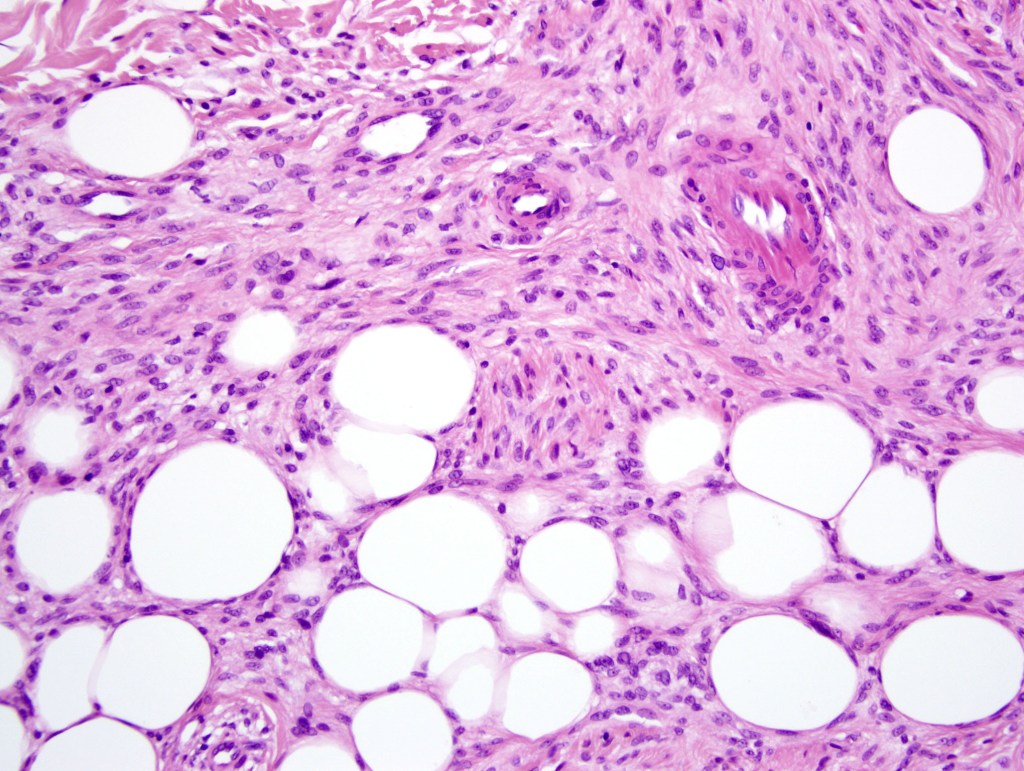

•Invasive tumor (lentigo maligna melanoma) typically characterized by a spindle cell population

•Desmoplastic and neurotropic melanoma in a significant number of cases